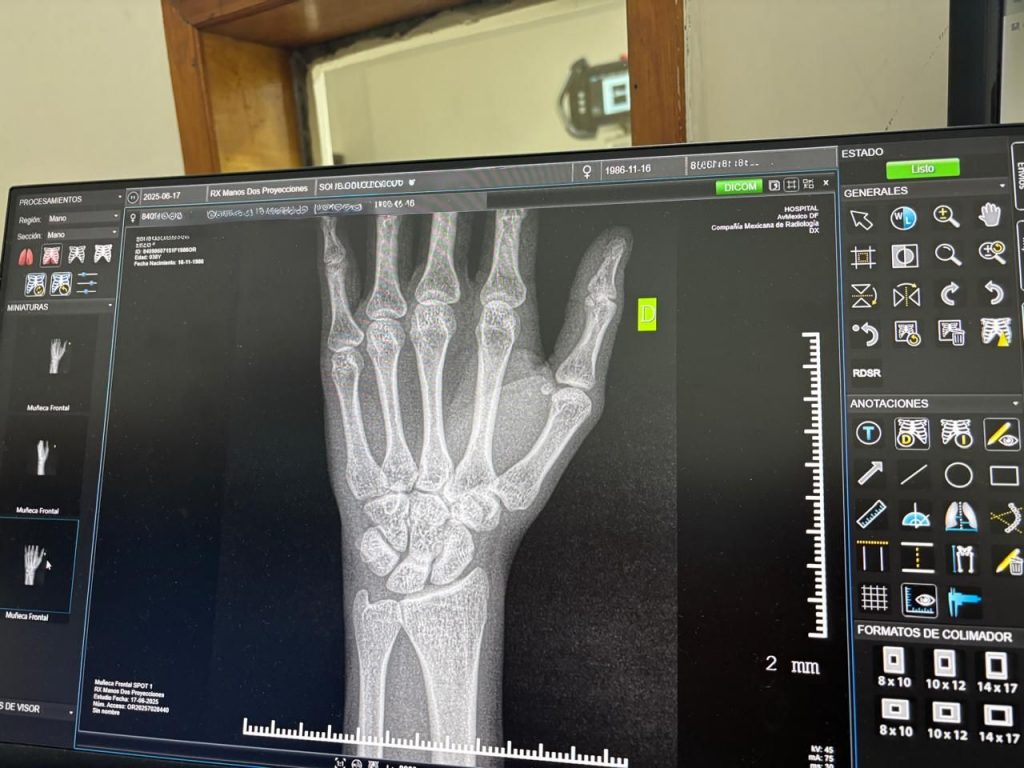

El coordinador de Atención Médica en Primer Nivel, doctor Julio Francisco Hernández Carrillo, explicó que la falta de cuidado en esta área puede derivar en padecimientos como osteopenia u osteoporosis, condiciones que debilitan los huesos y aumentan el riesgo de fracturas, en muchos casos sin síntomas iniciales.

Señaló que es importante acudir a valoración médica ante molestias persistentes, dolor sin causa aparente, fracturas frecuentes o disminución progresiva de la estatura.